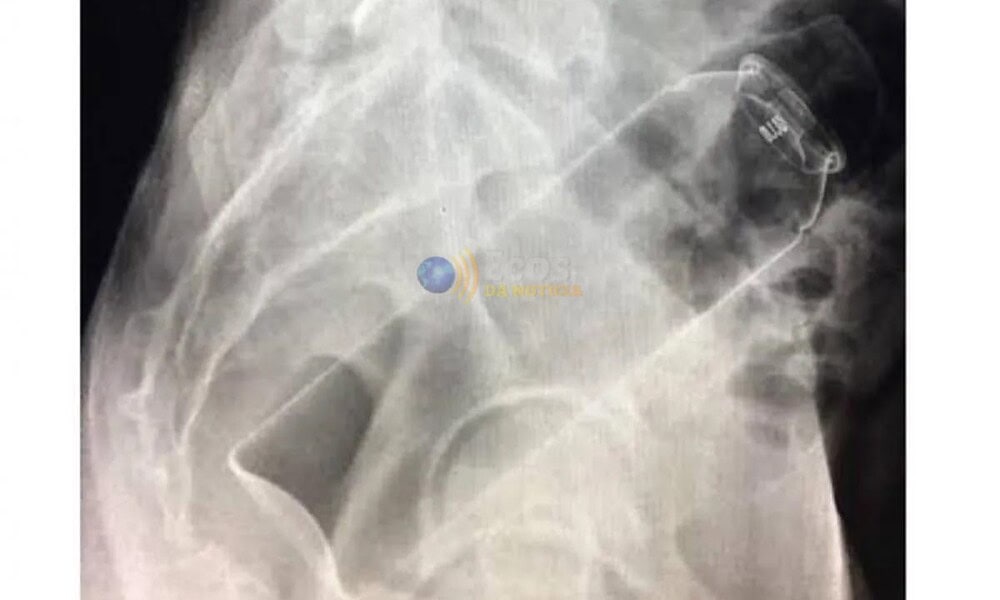

No local, a equipe médica realizou um procedimento para remover o desodorante, que foi concluído com sucesso. O empresário permaneceu em observação por algumas horas e recebeu alta ainda durante a madrugada, após avaliação dos profissionais de saúde.